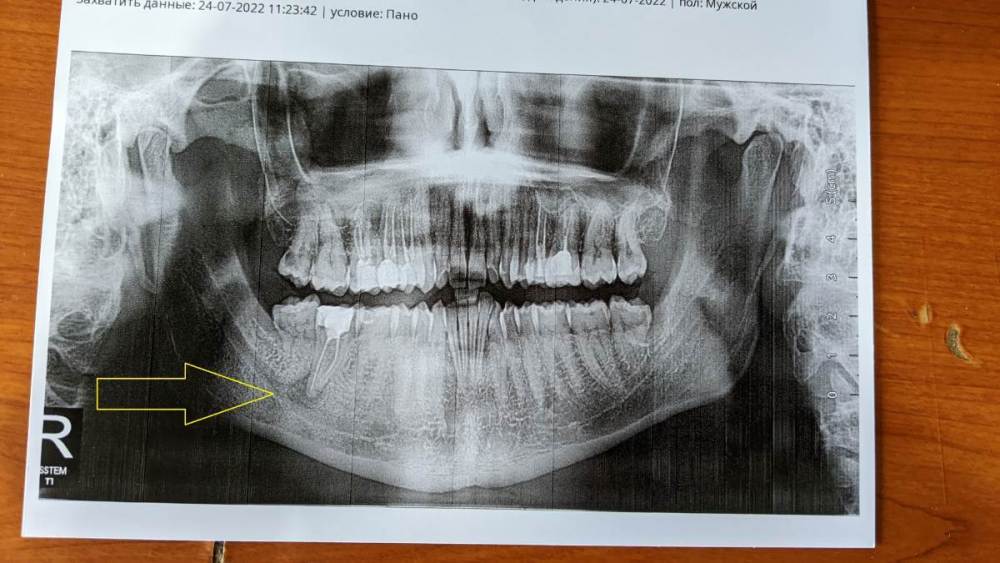

c4shurik Опубликовано 24 июля, 2022 Поделиться Опубликовано 24 июля, 2022 Всем привет! Подскажите пожалуйста! Вобщем я заболел бронхитом, у меня начал долезать зуб мудрости и начал болеть соседний с зубом мудрости зуб. Бронхит почти закончился, зуб мудрости успокоился, а вот соседний зуб уже неделю не дает мне покоя. Зуб этот леченый, корни пломбированы. Пару раз уже было что он болел когда я простужался или отравлялся, но обычно не сильно и за пару дней проходило. В стоматологии сказали нужно открывать каналы и пробовать лечить и что результат 50\50, возможно поможет а возможно придется удалить зуб. Подскажите пожалуйста как вы видите ситуацию? И почему зуб с пломбированными каналами так себя ведет? Ссылка на комментарий

c4shurik Опубликовано 27 июля, 2022 Автор Поделиться Опубликовано 27 июля, 2022 24.07.2022 в 15:20, red_butler сказал: Здравствуйте, в системе корневых каналов инфекция, требуется повторное лечение. Ищите грамотного врача. Кажется один канал не запломбирован да Ссылка на комментарий

red_butler Опубликовано 27 июля, 2022 Поделиться Опубликовано 27 июля, 2022 3 часа назад, c4shurik сказал: Кажется один канал не запломбирован да это не важно, нужно все каналы обрабатывать Ссылка на комментарий